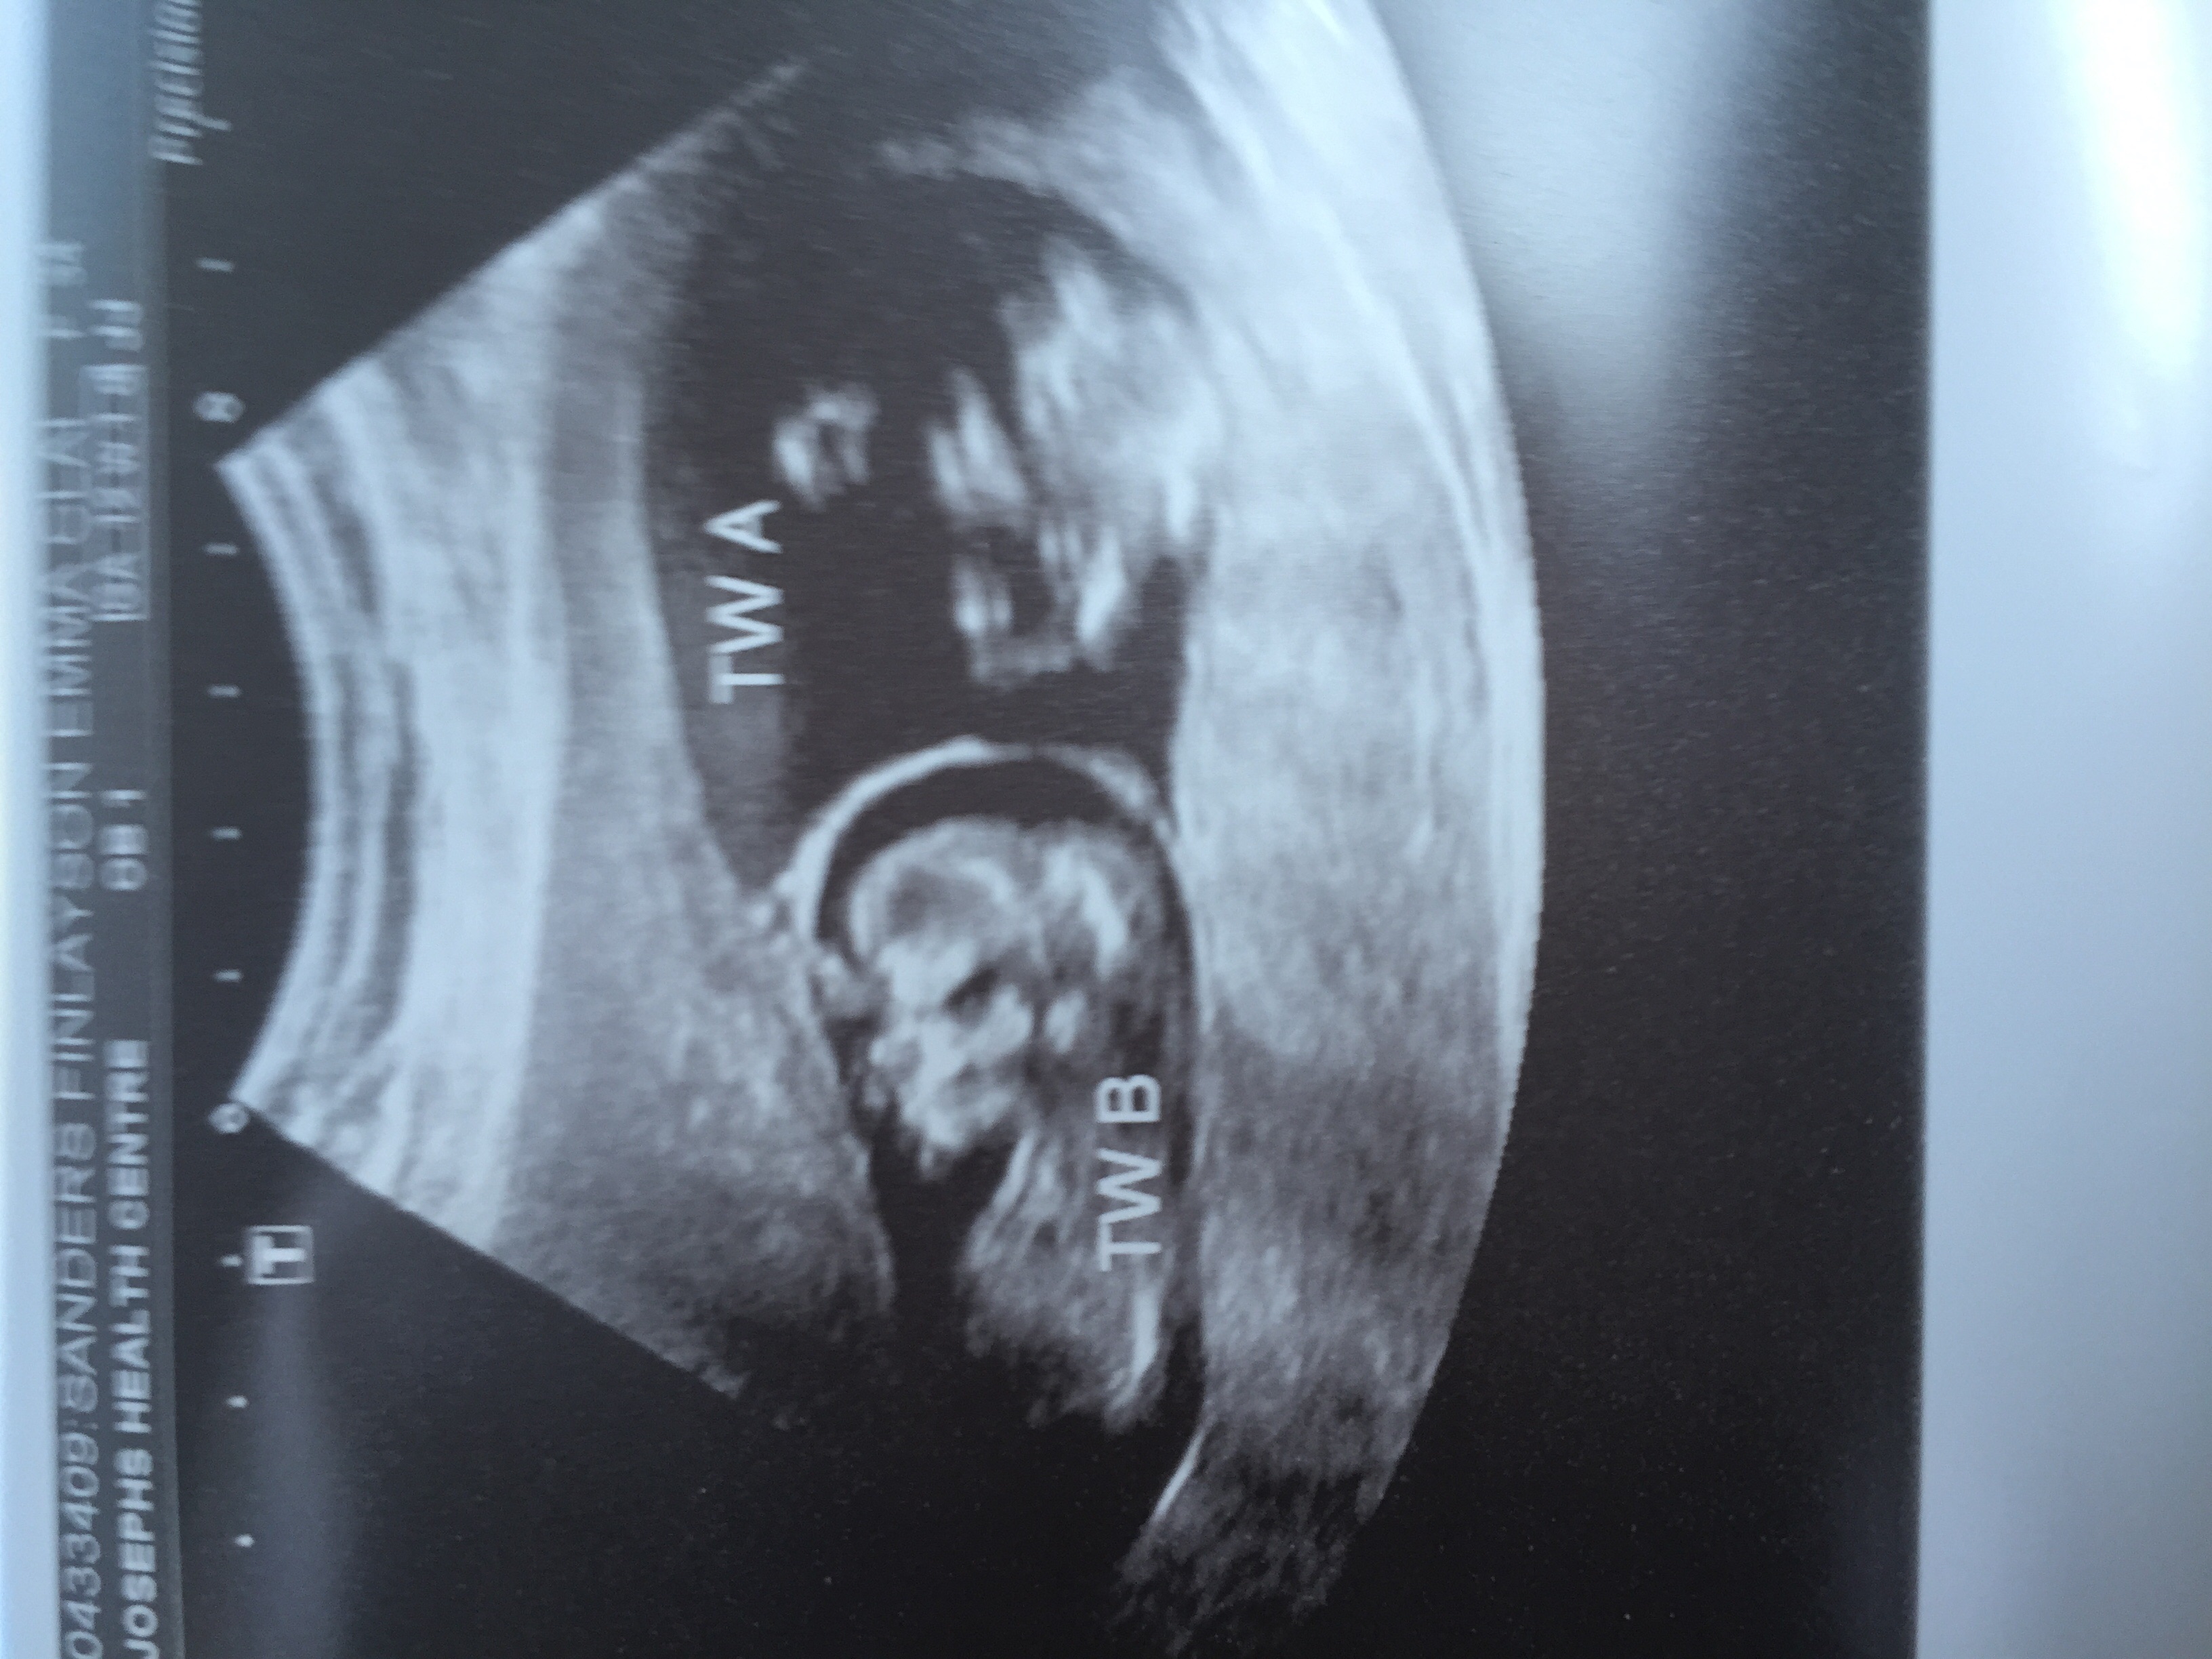

We had our first u/s yesterday and got to see this little one at 10weeks exactly! We got a little wiggle out of him/her. So cute!